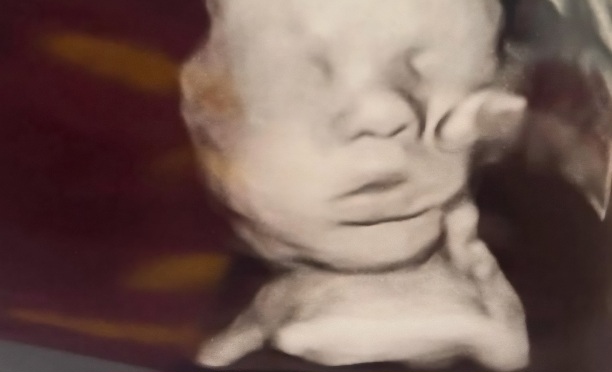

अमेरिका की रहने वाली 33 वर्षीय अमांडा फोस्टर ने जब अल्ट्रासाउंड रिपोर्ट देखी तो तस्वीर में कुछ बहुत ज्यादा हैरान करने वाली चीज दिखाई दी. अमांडा का मानना है कि उन्हें अपने अजन्मे बच्चे के सिर पर भगवान का हाथ दिखाई दिया, जो उसे सहला रहा था. महिला ने खुद इसकी तस्वीर शेयर करते हुए सोशल मीडिया पर अन्य लोगों को इस घटना के बारे में बताया है.

महिला ने लिखा,’हमने और कई अन्य लोगों ने मिलकर बहुत दुआ की. जब हमने एक स्पेशलिस्ट से दोबारा जांच करवाई तो बीमारी पूरी तरह से गायब थी.’ अमांडा का कहना है कि उन्होंने अपने बेटे की अल्ट्रासाउंड रिपोर्ट में एक हाथ देखा जो बच्चे के सिर को सहला रहा था. उनकी छोटी बेटी ने सबसे पहले पूछा,’ये हाथ किसका है?’ इसके बाद उनके पति ने भी देखा और कहा कि यह भगवान का हाथ हो सकता है जो उनके बेटे की रक्षा कर रहा है.’

हालांकि महिला के जरिए किए जा रहे दावे को लेकर सोशल मीडिया यूजर्स का कुछ और ही मानना है. कुछ यूजर्स कह रहे हैं कि यह बच्चे का ही हाथ है, जो अलग नजर आ रहा है.